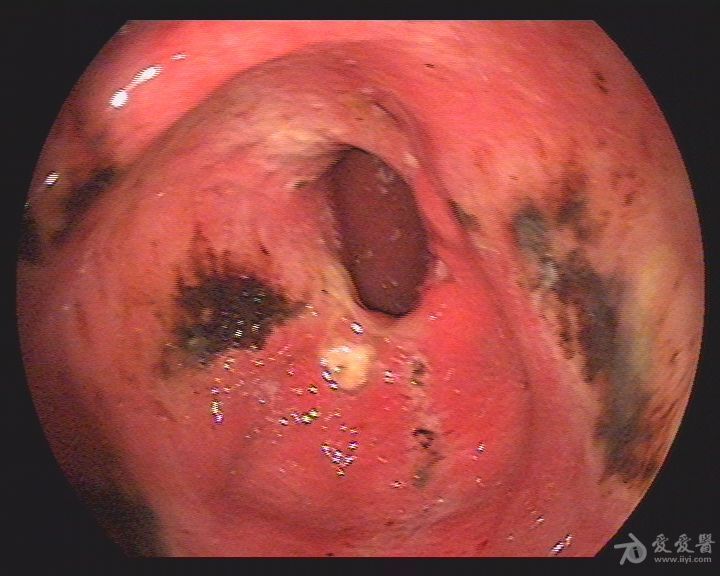

胃窦病变,看看是什么病变?

图片尺寸768x576